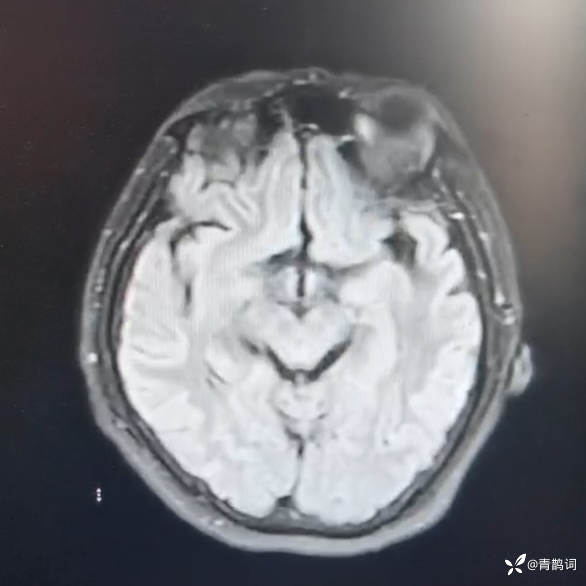

简要病史:患者于就诊前4个月出现反应迟钝,逐渐加重,目前认识家人,生活可自理,外出后可自行回家,无头痛头晕及二便失禁。曾就诊于外院,考虑脑炎可能性大。未与特殊处置。既往无特殊病史。

查体:神志清楚,反应迟钝,计算力下降(93-7=84)。四肢肌力肌张力正常,脑膜刺激征阴性。

头部磁共振DWI及FLAIR:

请结合病史及辅助检查,分析患者的诊断思路~